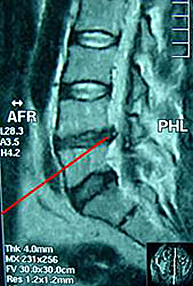

Dado que en el interior de la columna lumbar se alojan las raíces nerviosas, si el desgaste vertebral no afecta al canal por donde discurren estas raíces, no habrá ningún tipo de compresión y por tanto la enfermedad se manifestará con dolor lumbar, pero sin irritación de ningún nervio de las extremidades. Habrá lumbalgia pero no ciática. No obstante, es habitual que en estadios avanzados del proceso degenerativo lumbar se produzca compresión de alguna raíz nerviosa y la lumbalgia con ciática sea un síntoma rutinario.

La configuración anatómica de una vértebra implica la existencia en su parte media de un orificio denominado agujero vertebral por cuyo interior discurre el sistema nervioso. La superposición de las diferentes vértebras origina que la suma de todos estos orificios constituyan el llamado canal lumbar. La disminución de sus diámetros constituye un cuadro patológico que se conoce como estenosis de canal lumbar.